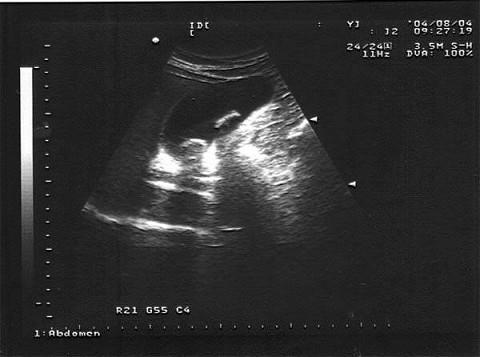

问题 女,28岁,经常上腹不适。声像图如图所示,诊断为?(?)

选项 A.胆囊蛔虫 B.胆囊结石 C.胆囊腺瘤 D.胆囊内胆汁淤积 E.胆囊癌

答案 B